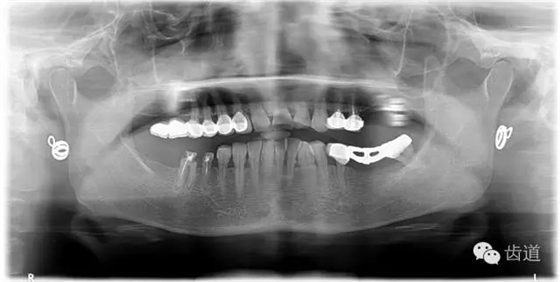

1、術(shù)前全景片

2、45,46術(shù)前片顯示根管上段充填物,根管影像不清晰,少許根尖暗影

3、34術(shù)前片顯示遠(yuǎn)中面暗影近髓

1、治療前